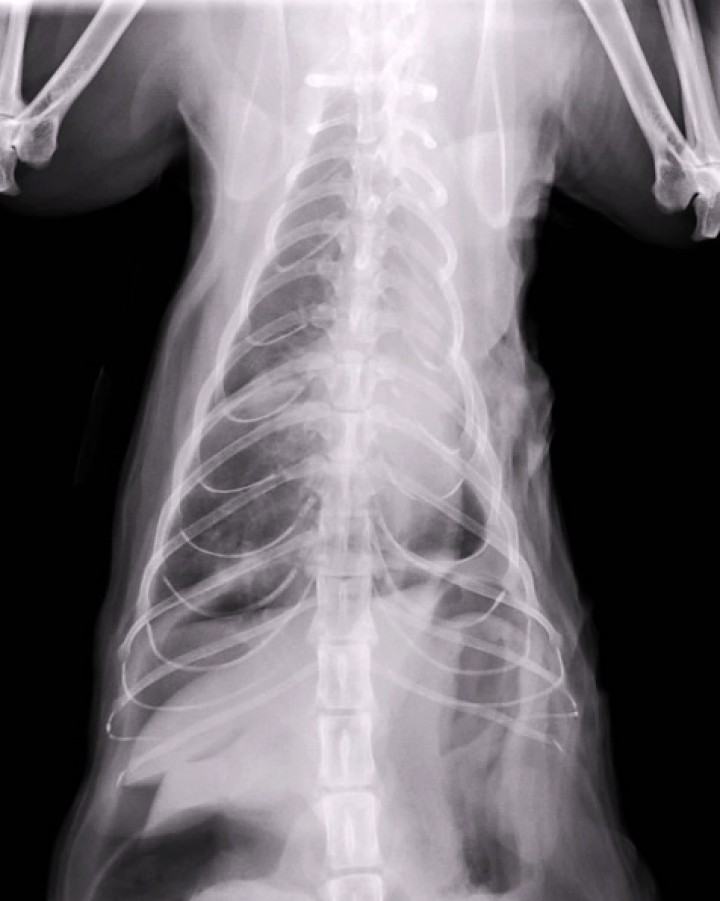

Se realiza hematología rutinaria y perfil bioquímico prequirúrgico (creatinina, proteínas totales, glucosa, GPT), estando todos los parámetros dentro del rango de referencia. Se procede a anestesia general con propofol i.v. (Propofol lipuro 1%, Braun Vet-care, Barcelona) a dosis de 2 mg/kg posterior a premedicación vía intramuscular con metadona (0,3 mg/kg, Metasedin inyectable 10 mg/ml, Braun, Barcelona), medetomidina (10 µg/kg, Medetor, solución inyectable 1 mg/ml, Virbac, Barcelona)) y midazolam (0,1 mg/kg, Midazolam inyectable 5 mg/ml, Normon, Tres Cantos). Se inicia ventilación mecánica a 12 respiraciones /minuto con 8 cmH de H2O con el ventilador en modo de control de presión. Se procede a toracotomía en sexto espacio intercostal izquierdo. Esta localización permite una óptima exposición del hilio del lóbulo pulmonar caudal.[ Tobias K, Johnston S. Small Animal Surgery. 1st edition. Chapter 103 p:1752-1768. 2011. Elsevier. St Louis, Missouri, USA. ] Se accede a cavidad torácica tras sección de los músculos intercostales en su región media para evitar dañar vasos o nervios, desde la región próxima a la articulación costovertebral en dorsal hasta la unión costocondral en ventral. Se emplea un separador de finochietto para exponer el campo quirúrgico. Se observa un pulmón completamente atelectásico con presencia de una bulla en extremo distal (Fig. 4). Se incrementa progresivamente la presión positiva del ventilador mecánico,[ Hopper K, Powel LL. Basics of mechanical ventilation for dogs and cats. Vet Clin North Am Small Anim Pract 2013. 43(4): 955-969. [PubMed] ] desde 8 cmH2O a 10 cmH2O y, posteriormente, a 12 cmH2O sin lograr reinsuflar el pulmón afectado. Se aplica una PEEP (Presión Positiva al final de la Espiración) inicialmente de 2 cmH2O y, posteriormente, de 4 cmH2O, de nuevo sin obtener resultados. El pulmón permanece completamente atelectásico, por lo que se procede a neumonectomía completa del pulmón izquierdo. Para ello se emplea sutura no reabsorbible de nylon monofilamento 3/0, realizándose ligadura manual de la arteria pulmonar izquierda, el bronquio principal izquierdo y la vena lobar izquierda. Estas estructuras se ligan individualmente. Se realizan tres ligaduras en el bronquio con unos 2 mm de separación entre ellas y dos ligaduras con unos 4 mm de separación en ambos vasos. Para facilitar la ligadura se realiza clampaje con un clamp vascular curvo y se realiza una ligadura distal y otra proximal en el caso de los vasos, y dos ligaduras proximales y una distal en el caso del bronquio. Una vez extirpado el pulmón, el extremo libre del bronquio principal se sutura con patrón continuo para evitar cualquier fuga de aire. Una vez reparada la pared torácica se realiza drenaje torácico para eliminar el gas presente en la cavidad empleando un catéter de 14 gauges insertado en región dorsocaudal respecto a la toracotomía. Se fija el catéter con sutura de nylon 3/0, lo que permite repetir el drenaje una vez concluida la sutura cutánea.

<p>Imagen de la toracotomía intercostal izquierda que muestra pulmón atelectásico y presencia de bulla enfisematosa en su polo distal (estrella).</p>

Figura 4

Imagen de la toracotomía intercostal izquierda que muestra pulmón atelectásico y presencia de bulla enfisematosa en su polo distal (estrella).